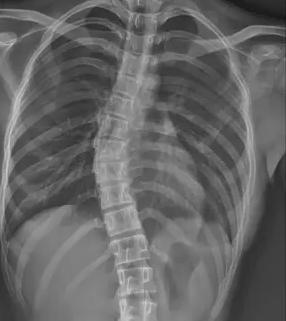

在數字化學習與久坐生活模式普及的當下,青少年脊柱側彎正以驚人速度蔓延,成為威脅青少年健康的 “沉默流行病”。國家衛健委最新數據顯示,我國 10-18 歲青少年脊柱側彎總體患病率已達 1.2%,2016-2024 年間發病率近乎翻倍。值得關注的是,16-18 歲青少年群體患病率顯著高于低齡組,女生患病風險更是男生的 1.6 倍。地域差異同樣嚴峻,西部欠發達地區如甘肅天??h的疑似病例比例遠超上海楊浦區,暴露出醫療資源分布不均的深層矛盾。

當前青少年脊柱側彎診療體系面臨系統性困境。在篩查環節,傳統 X 線測量 Cobb 角雖為金標準,但輻射風險限制其大規模應用;現有初篩手段假陽性率高達 35%,而低輻射智能篩查技術在基層醫院普及率不足 12%,導致大量病例漏診。疾病管理鏈條存在顯著斷層,Cobb 角<10° 的輕癥患者因缺乏標準化干預方案,錯失黃金矯正期。保守治療領域,支具治療依從性不足 40%,定制精度誤差超 15%,全國注冊矯形師缺口達 83%;物理治療資源配置失衡,70% 的基層醫療機構尚未建立規范康復訓練體系。

針對上述痛點,醫療科技企業與科研機構正聯合構建智慧防治體系。迪納醫療研發的全幅 Dira-DUC 技術,通過 AI 輔助三維重建實現單次 0.02mSv 低劑量成像,較傳統設備輻射量降低 87%。其自主研發的脊柱側彎風險預測模型,整合 120 萬例臨床數據,可精準識別高危人群,篩查準確率提升至 92%。診療環節引入智能 Cobb 角測量算法,將人工測量誤差從 ±5° 壓縮至 ±1.2°。在支具治療方面,智能監測支具內置壓力傳感器與物聯網模塊,實時反饋佩戴數據并生成個性化調整方案。物理治療領域,標準化訓練課程已納入國家衛健委基層康復指南,配備 AI 動作捕捉系統的智能訓練艙正在全國 127 家縣級醫院推廣。